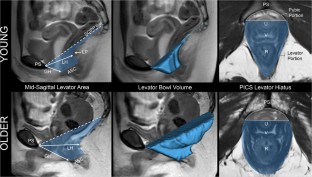

A case–control study was conducted from June 2017 to August 2018 comparing two groups of nulliparous women: <40 years old and ≥ 70 years old. Clinical evaluation included POP-Q, instrumented speculum testing, and handgrip strength. Dynamic 3D-stress MRI was performed on all women to obtain genital and levator hiatus (LH) lengths, LH area, and levator bowl volume. LH shape was quantified using a novel measure called the “V-U index.” Pubovisceral muscle (PVM) cross-sectional area (CSA) was also measured. Bivariate comparisons between the two groups were made for all variables. Effect sizes were calculated for MRI measurements.

Twelve young and 9 older nulliparous women were included. Levator bowl volume at rest was 83% larger in older women (108.0 ± 34.5 cm3 vs 59.2 ± 19.3 cm3, p = 0.001, d = 1.82). MRI genital hiatus at rest was larger among the older group (2.7 ± 0.6 cm vs 3.5 ± 0.6 cm, p = 0.007, d = 1.34). V-U index, a measure of LH shape where 0 = “V” and 1 = “U,” differed between groups indicating a more “U”-like shape among older women (0.71 ± 0.23 vs 0.35 ± 0.18, p = 0.001, d = 1.72). Handgrip strength was lower in the older vs young group (23.2 ± 5.2 N vs 33.4 ± 5.2 N, p < 0.0001); however, the Kegel augmentation force and PVM CSA were similar (3.2 ± 1.1 N vs 3.3 ± 2.2 N, p = 0.89, and 0.8 ± 0.3 cm2 vs 0.7 ± 0.2 cm2, p = 0.23 respectively).

Levator bowl volume at rest was over 80% larger among older women, reflecting a generalized posterior distension with age.

Nandikanti L, Sammarco AG, Chen L, Ashton-Miller JA, DeLancey JO. Levator bowl volume during straining and its relationship to other levator measures. Int Urogynecol J. 2019; https://doi.org/10.1007/s00192-019-04006-8.